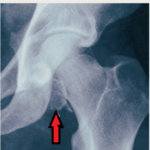

Femoral Neck Fractures In Children

Courtesy: Dr Ashok Shyam, Dr. Alvin Crawford, Ortho TV Pediatric Femoral Neck Fractures Overview Rare injuries accounting for approximately 1% of pediatric orthopedic fractures Usually caused by high-energy trauma Trivial trauma should raise suspicion for: Pathological fracture Insufficiency fracture Common Pathological Causes Unicameral bone cyst Chondroblastoma Osteosarcoma Epidemiology More common in boys Incidence in […]